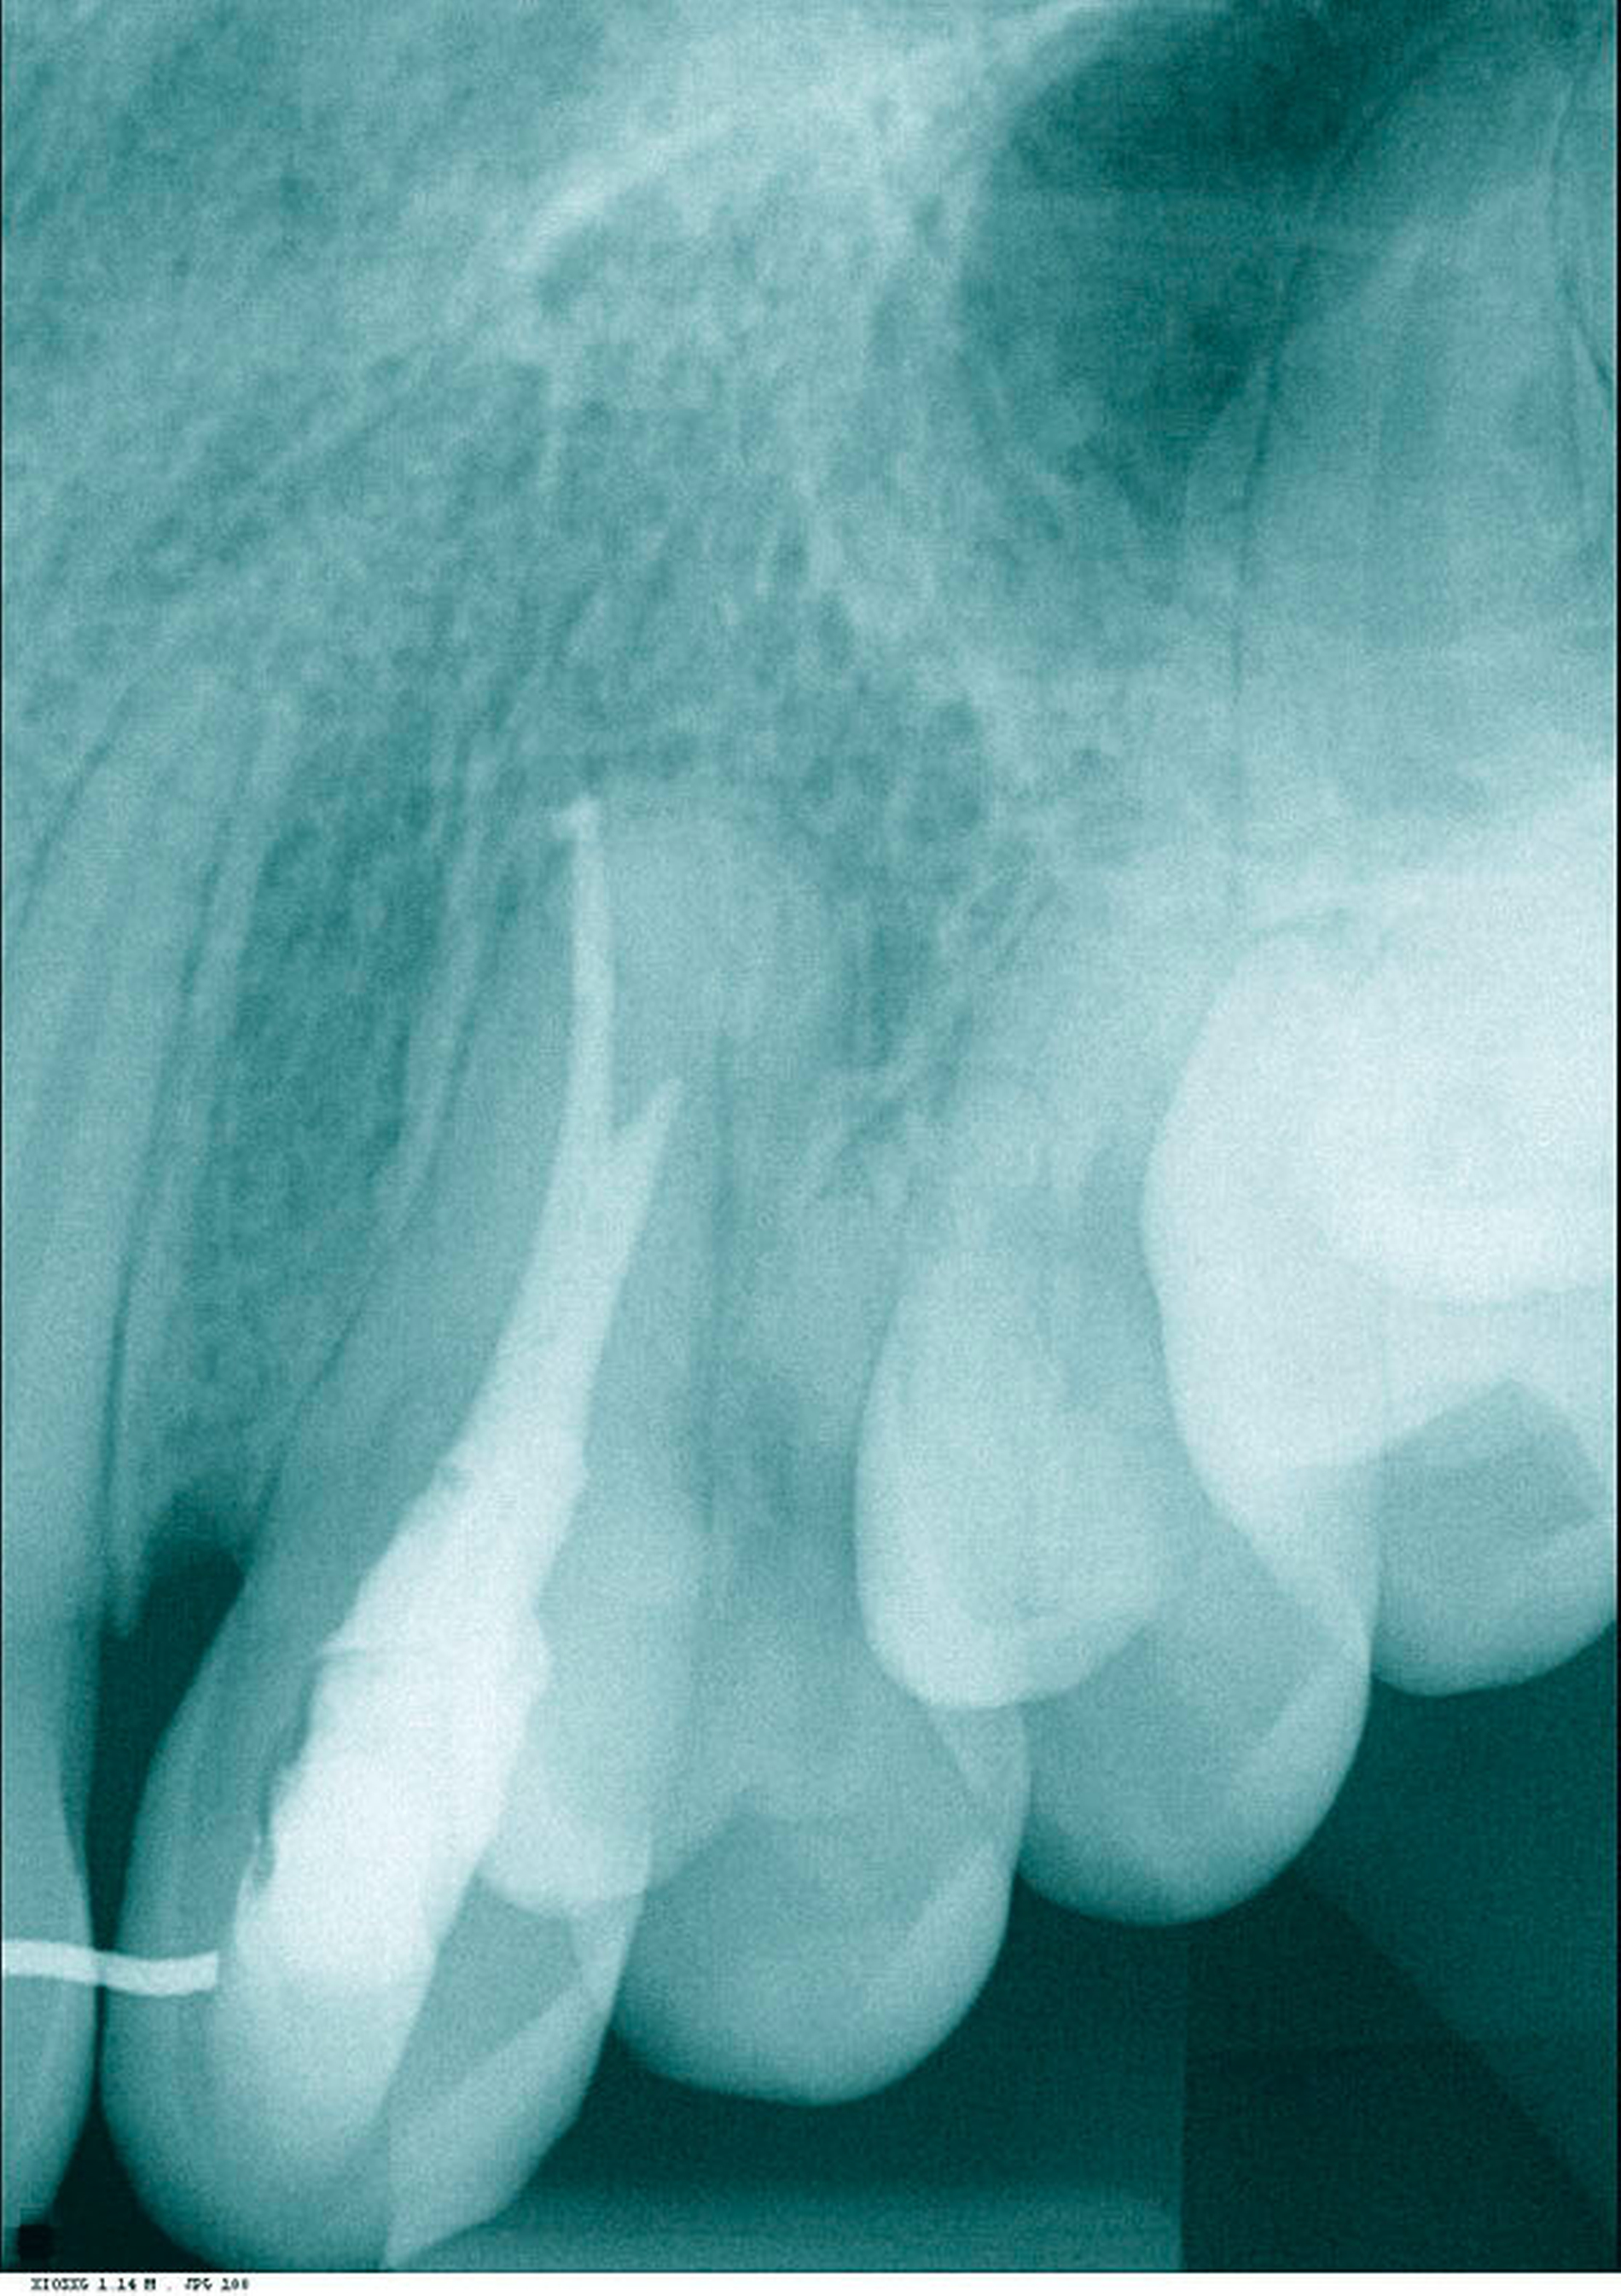

Der 17-jährige Patient stellte sich mit nicht auffindbarem Wurzelkanal Zahn 23 vor. Er war allgemeinanamnestisch unauffällig. Zum Zeitpunkt der Überweisung war die Trepanation bereits erfolgt und der Zahn provisorisch gefüllt. Ein präoperatives Röntgenbild, auf dem keinerlei Kanalstrukturen erkennbar waren (Abbildung 1) sowie ein OPTG (Abbildung 2) lagen vor. Der Patient klagte über spontanen Schmerz, der Zahn war perkussionsempfindlich, reagierte nicht auf den Kältetest. Der Klopfschall war unauffällig, der vestibuläre Knochen im apikalen Bereich druckschmerzhaft. Die Diagnose lautete symptomatische apikale Parodontitis.

Es erfolgte die Inspektion unter dem OP-Mikroskop. Klinisch zeigte sich kein Anhalt auf Kanalstrukturen. Es erfolgten zwei zeitintensive Sitzungen, in denen der Wurzelkanal nicht dargestellt werden konnte und der Zahn, trotz größter Vorsicht und Verwendung des Mikroskops, perforiert wurde. Die Perforation war vestibulär im mittleren Kanaldrittel nach einer Länge von 18 mm lokalisiert (Abbildungen 3 und 4). Die Therapieentscheidung fiel daraufhin zugunsten einer „Guided Endodontics“-Behandlung.